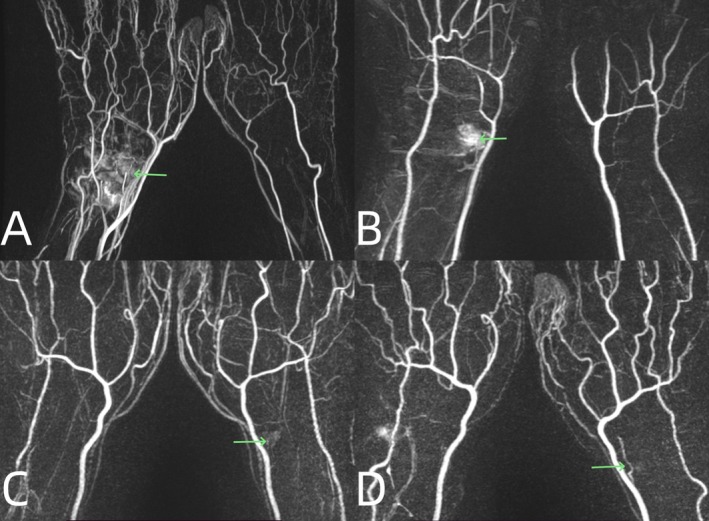

Methods: This was a prospective study. Between 2022 and 2023, contrast-enhanced magnetic resonance angiography and gadolinium-enhanced magnetic resonance imaging were performed in 32 patients (28 males and 4 females) with scaphoid fractures. The average age was 35 years (ranges: 15-74 years). We observed the accumulation and filling time of contrast media, and measured the diameters of extraosseous arteries as well as the signal intensity of intraosseous perfusion. The Mann-Whitney U-test, student's t-test, and Friedman test were used, respectively.

Results: 31 of 32 patients showed contrast media accumulation in the wrist joints on the affected sides. The filling time of contrast media on the affected sides was 5.6 (6.05-1) s quicker than on the healthy sides. The diameters of the radial arteries on the affected side increased by 12.8% (SD, 18.4%) compared to those on the healthy side (p = 0.002). All the patients had visible scaphoid nutrient arteries originating from the radial arteries on the affected side. The number of visible arteries on the healthy side was lower. Blood supply to the scaphoid was not related to the patient's sex, injury side, or fracture site. The increase in blood supply at the proximal fragment in older patients was less than that in young individuals (p = 0.015). Blood supply to the proximal and distal fragments of the scaphoid increased after fracture (p < 0.05). Within 1 month after the fracture, the increase in blood supply at the proximal fragment was less than that at the distal fragment, and it increased significantly after 1 month (p = 0.014). However, long-term nonunion (more than 4 years) leads to a decrease in proximal blood supply.